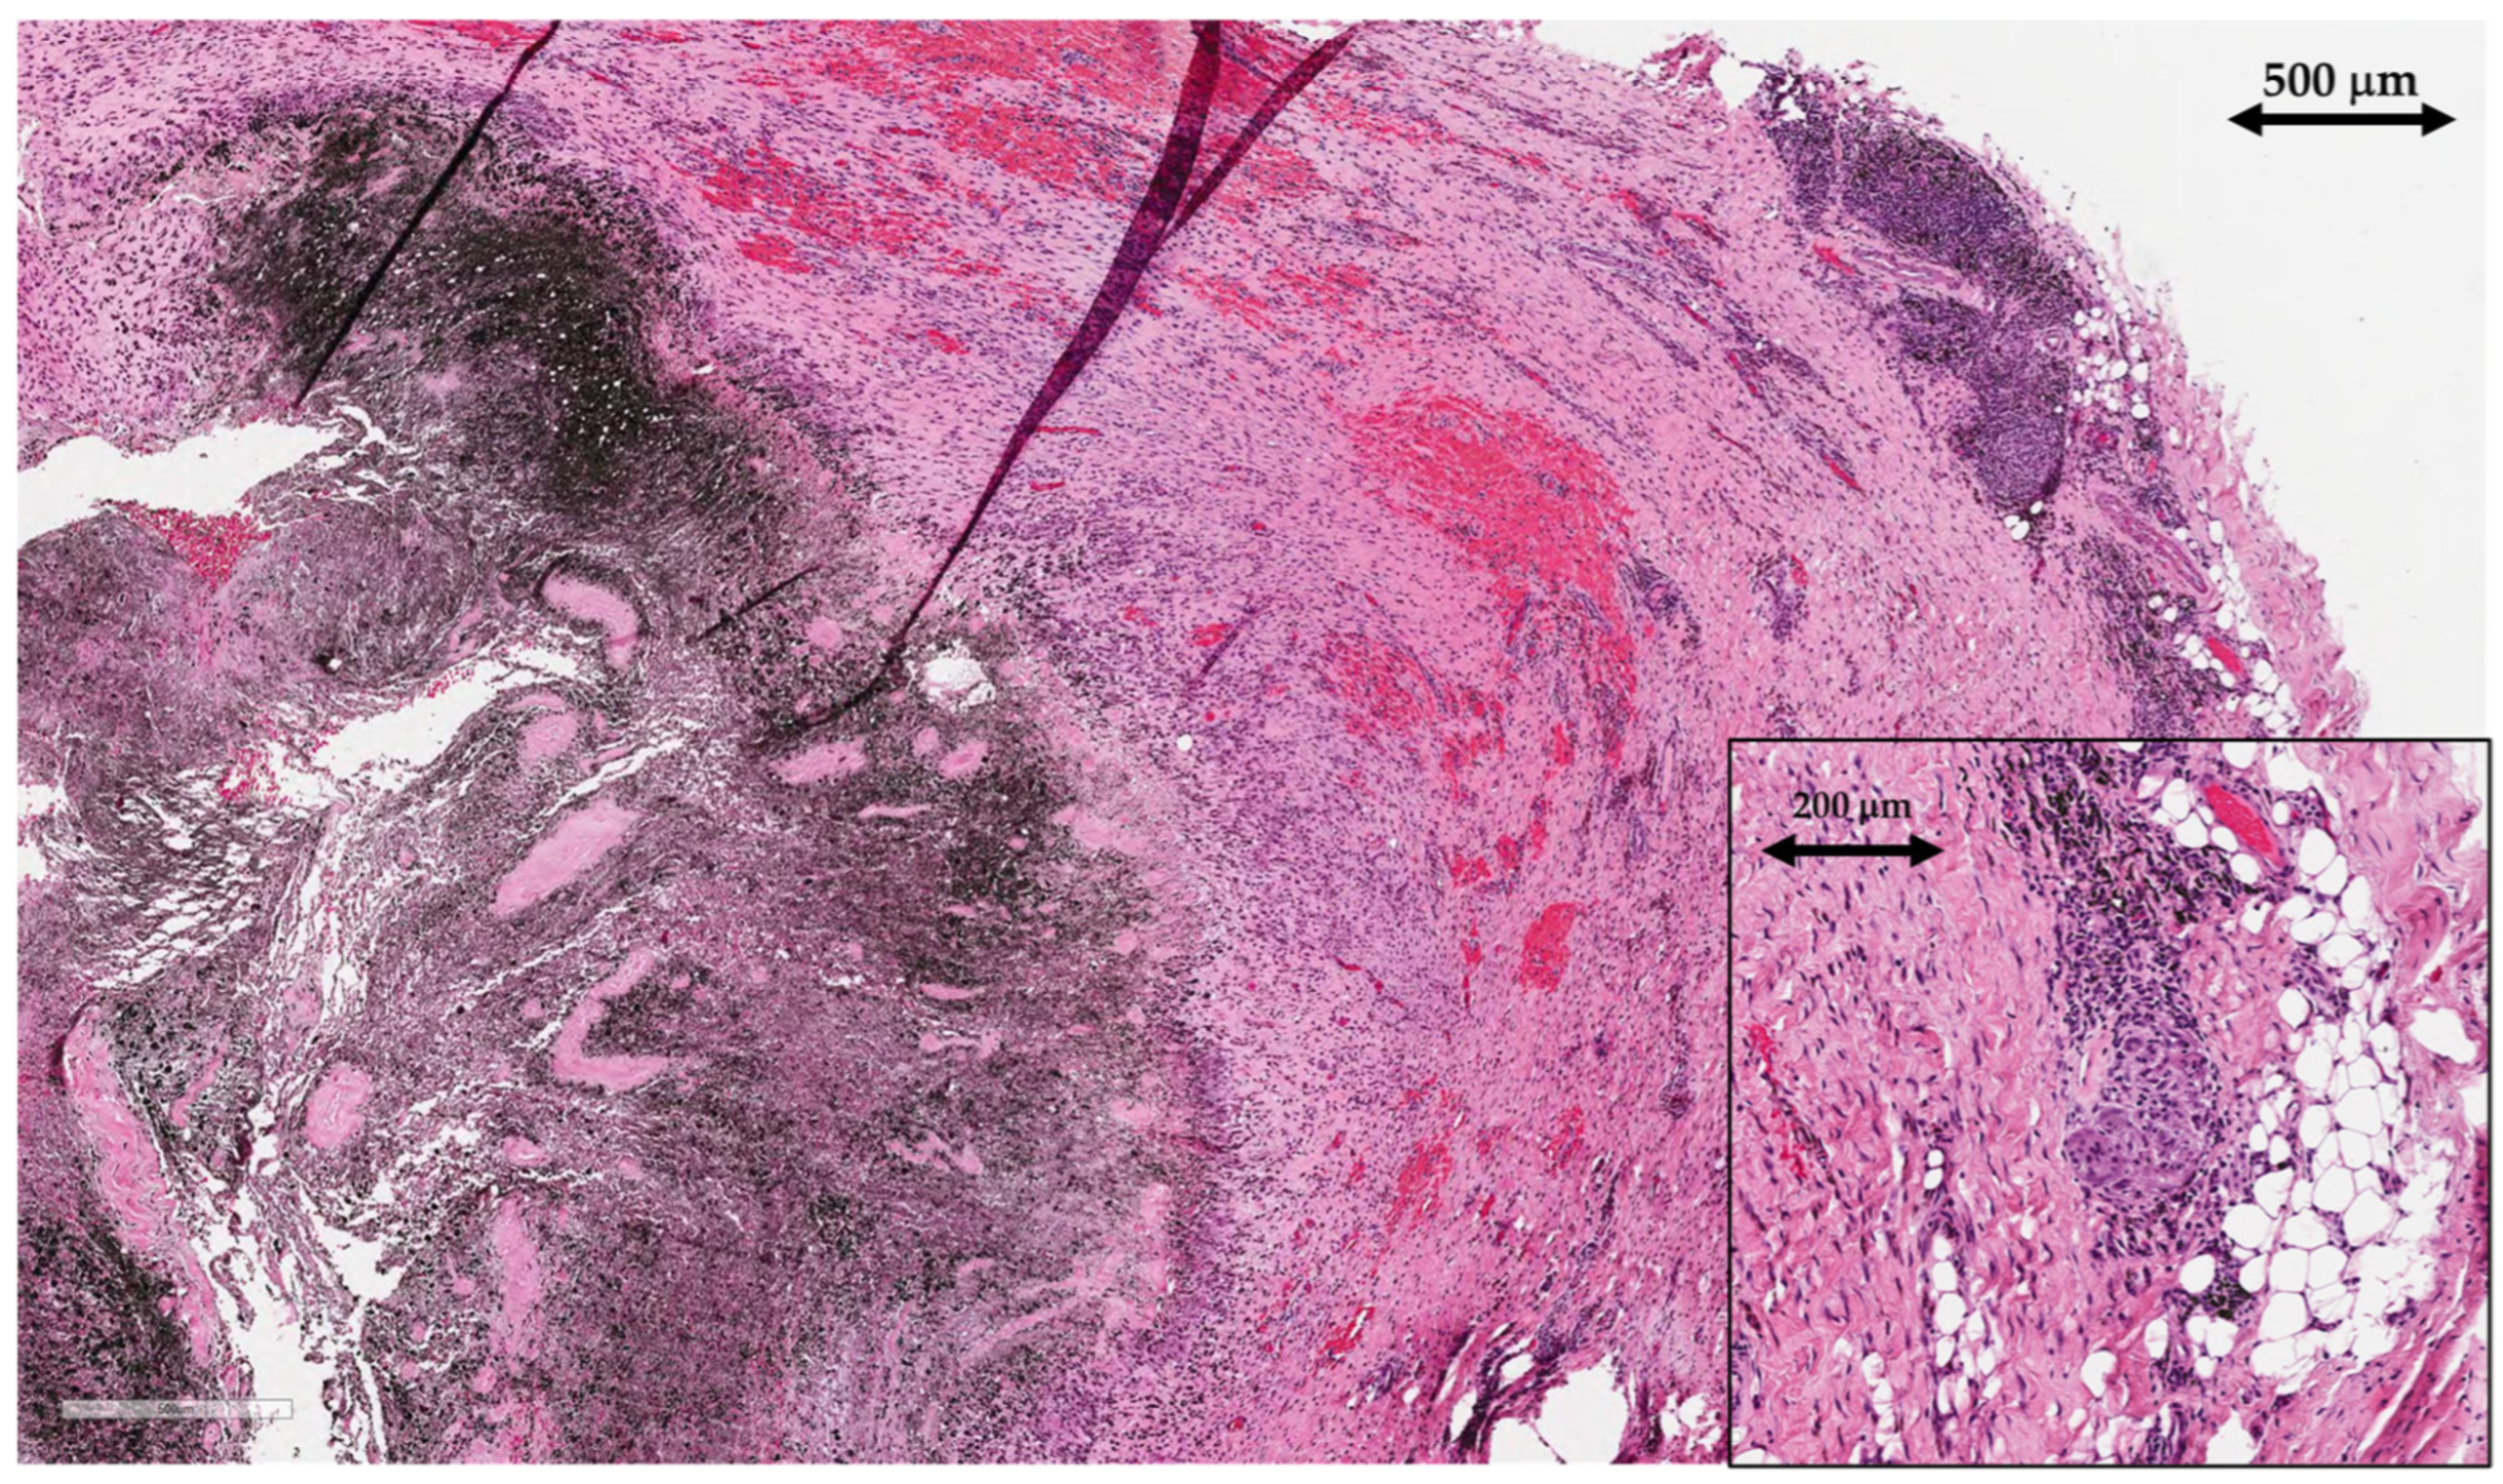

Tissue samples of periprosthetic soft tissue, that gave a macroscopic impression of pseudotumors were sent to the pathology lab for histological analysis. Tissue samples were of irregular shapes, soft, greyish brown to black color and up to 4 cm in size. Microscopic examination showed areas of necrotic tissue and fibrin depositions admixed with abundant metallic microparticles (Figure 6). There was extensive infiltration with predominantly macrophages, containing metallic micro and macroparticles as well as areas of granulomatous inflammatory reaction with foreign-body giant cells. Lymphoplasmacytic infiltrate was present but there were no granulocytes, indicating the absence of acute inflammation and therefore excluding infection.

After joint replacement surgery, regenerated synovial tissue and the periprosthetic membrane are referred to using the term “synovial-like interface membrane” (SLIM). Histological findings of SLIM pathology are classified into groups that aid the recognition of underlying pathophysiological mechanisms leading to implant failure. Based on the International Expanded SLIM Consensus Classification, the patient had a wear-induced synovitis/SLIM, leading to adverse local tissue reaction to implant wear particles (type VI) with a predominantly macrophagic pattern with absent or minimal lymphocytic response [13]. The patient did not meet criteria for periprosthetic joint infection (no neutrophils present in the tissue).

Figure 6. Histopathological findings of synovial-like interface membrane (SLIM), including areas of necrosis with abundant deposits of metallic micro and macroparticles (left), surrounded with layers of macrophages. Areas of haemorrhage (middle) and granulomatous inflammation with foreign-body giant cells (upper right corner, magnified in lower right corner) are also present (scale is written on each part of the image).